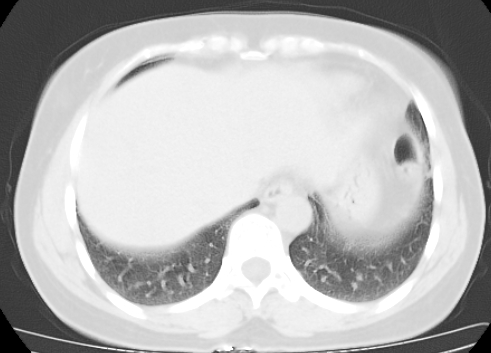

标题: CT25227:背部疼痛伴双侧胸壁痛2月,食欲差。 [打印本页]

标题: CT25227:背部疼痛伴双侧胸壁痛2月,食欲差。

肺结核并胸椎结核?请各位高手指教。

用椎体的条件来扫胸椎呀!考虑1左侧胸膜小结节形成2椎体结核并冷脓肿形成

考虑胸椎结核并椎旁软组织肿胀。

左肺结核灶,胸椎结核并冷脓肿。

左肺结核灶,胸椎结核并冷脓肿